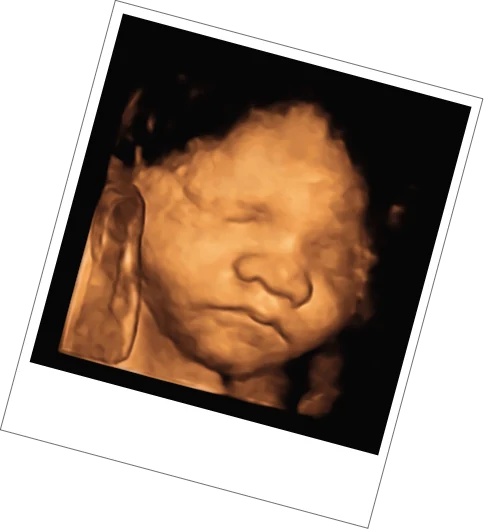

3D/4D Scan

24-32 Weeks

Between 24 – 32 weeks, we can offer 3D/4D scans which use advanced HDlive 3D/4D imaging to provide views of your baby in an alternative perspective. We can learn a lot about your baby through this method, focusing on progressive development and wellbeing observations. A complimentary baby sexing is included with this if your baby is properly positioned. The optimum time for this scan is between 26 to 29 weeks.